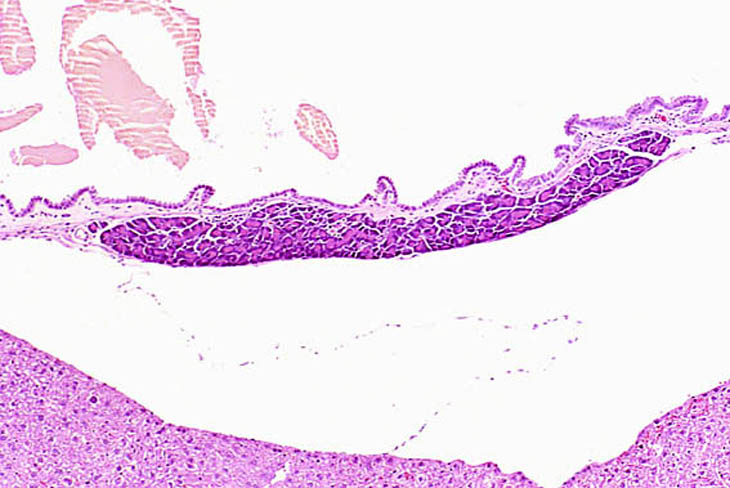

Ectopic pancreatic acinar tissue is present in the wall of the gallbladder.